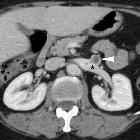

Asymptomatic

left renal vein aneurysm with thrombosis. Multiplanar reformatted images (b..d) from portal venous phase acquisition depicted the lesion (arrowheads) as a saccular outpouching of the left renal vein (*), with internal nonenhancing tissue (thin arrows) representing intraluminal thrombus.